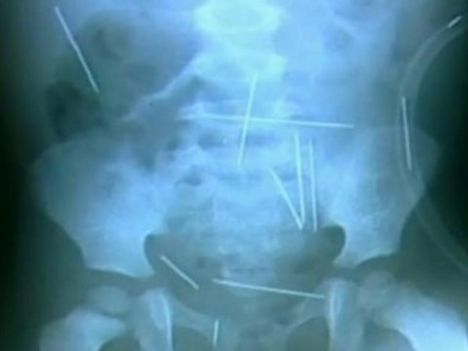

To je noro: dve leti staremu dečku v telo zapičili 50 igel!